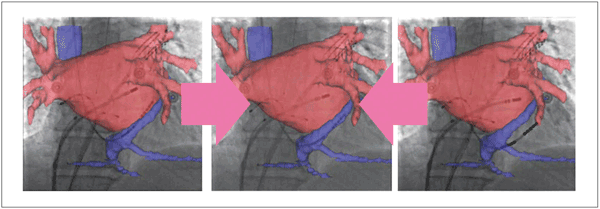

前述のECG gatingだけでもかなり良好な効果は得られるが,Image Stabilizationを併用することにより,さらに精度の高い補正が可能となる。この2つの技術をリアルタイムに組み合わせることではじめて,アブレーションカテーテルを3Dロードマップ画像上に“ロックオン”することが可能となり(図3),より安全で的確な手技に寄与できるものと確信している。

図3 ECG gatingとImage Stabilization

この2つの機能を組み合わせることで,アブレーションカテーテルを3D画像上に“ロックオン”することが可能となる。